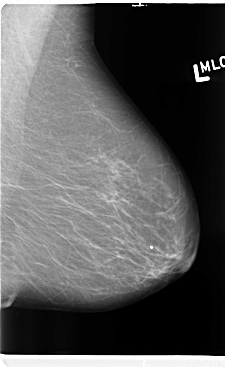

B_3140_1.LEFT_MLO

LEFT_MLO LINES 4760 PIXELS_PER_LINE 2920 BITS_PER_PIXEL 12 RESOLUTION 50 NON_OVERLAY